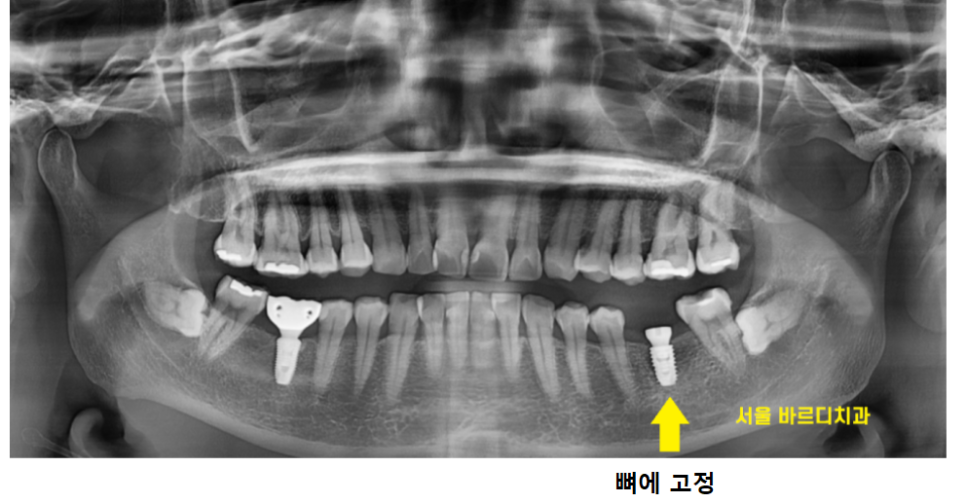

24.01.11

임플란트는 뼈에 고정되어있습니다.

자연치와 다른 특징중 하나가

충격을 흡수해주는 인대가 없다는 것이에요.

뼈에 고정되어 있는데다가

충격을 흡수해주는 장치까지 없으니

음식을 씹을때마다 충격이 고스란히 받게됩니다.

위아래로 씹는 힘에는 강하지만

좌우로 가는 힘에는 약합니다.

24.06.27

그래서 임플란트 후에

딱딱한 음식을 피하라고 하는 것은

이 옆으로 가는 힘을 줄여주기 위해서입니다.

그렇다면 보철물 크기가 크게 만들면

어떻게 될까요???

보철을 크게 만든다고 좋은게 아니에요~

과도한 힘이 임플란트에 자꾸 가해지게 되어서

임플란트 나사가 풀리거나

임플란트 뼈가 녹을 수 있습니다.